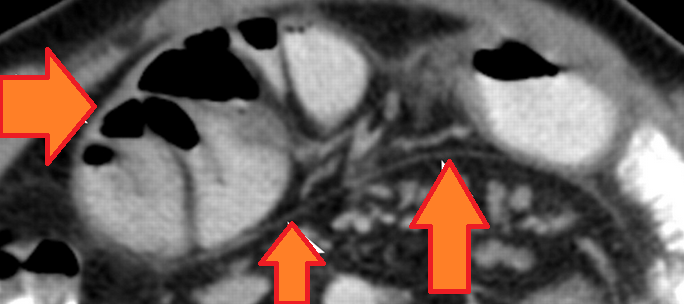

Ultrasound examination. Red arrows: Thickened peritoneum (Courtesy Dr. V. Penopoulos)